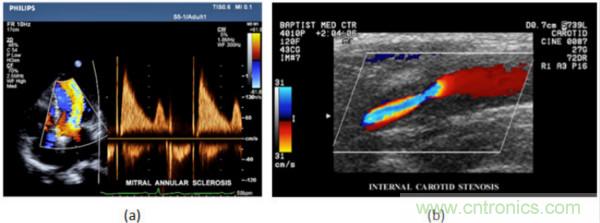

在CW和PW多普勒模式中,流信息是从一个聚焦声束中获得的,类似于A模式成像。在20世纪80年代,研究人员基于彩色多普勒技术完成了血流分布的二维信息可视化。彩色多普勒处理也是基于B模式/PW模式信号路径。从感兴趣区域收集多帧RF数据。由于感兴趣区域中的血液流动导致图像帧之间存在数据差异。相域中的自相关和时域中的互相关两种算法可从RF数据中提取数据方差(即血流速度和方向信息):。根据预定义的颜色渐变条相应地映射包括速度和方向的血流信息。通常,蓝色和红色代码分别识别朝向和远离换能器移动的血流。当流速增加时使用更亮的颜色,反之亦然。颜色映射的2D分布始终叠加在B模式图像上,以实时同时显示个体解剖结构和血流。它对于诊断心血管疾病,如血管闭塞和心脏瓣膜反流,极其有用。典型的彩色多普勒图像如下图所示,(b)显示颈动脉狭窄引起的血流流速变化。

图7.彩色多普勒成像:(a)以彩色多普勒和CW模式获得的图像(由Philips提供); (b)显示颈动脉狭窄的彩色多普勒(由GE提供)